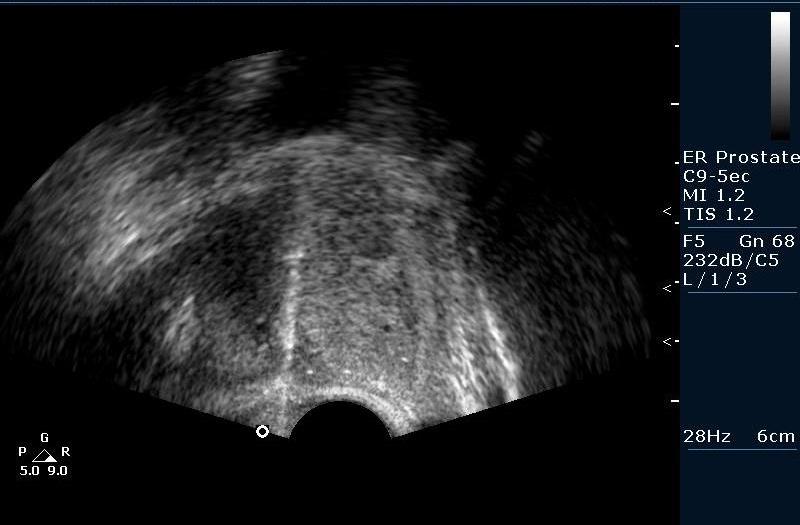

Биопсия предстательной железы под контролем Ультразвуковой визуализации. Рутинная практика в нашем отделении pадиологии, выполняется практически всем пациентам с повышенным уровнем ПСА (естественно, учитывая результаты осмотра урологов).

Биопсийная игла в железе (трепан биопсия)